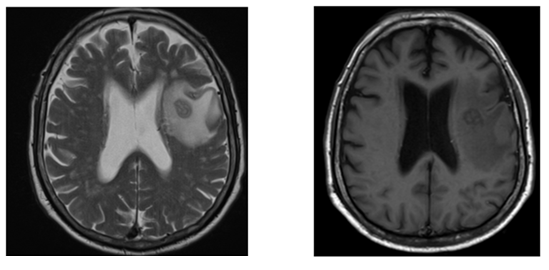

Se presenta el caso de un paciente de sexo masculino de 72 años con hipertensión arterial en tratamiento regular, sin otras patologías de base que acude por cuadro de 4 días de evolución de disartria y confusión leve de inicio brusco acompañado de desviación de la comisura labial más sialorrea. Refiere historia previa de meses de evolución de tos seca ocasional, leve pérdida de peso, más astenia y anorexia. Niega fiebre, cefalea, náuseas y vómitos. Al examen físico se constata parálisis facial derecha y mal estado de piezas dentarias sin otros datos de valor. Acude a centro asistencial donde solicitan tomografía axial computarizada (TAC) simple de cráneo donde se constata imagen hipodensa a nivel frontal izquierdo por lo que solicitan resonancia magnética nuclear (RMN) con contraste de encéfalo donde se observó lesión focal oval a nivel frontal izquierdo con signo de doble anillo y realce periférico en anillo en secuencia T2 (16x10x9,6 mm); volumen de 1ml, extenso edema perilesional. (Figura 1a; Figura 1b)

Figura 1a, b. Lesión focal oval bien delimitada a nivel frontal izquierdo con signo de doble anillo y con realce periférico en anillo en secuencia T2 y T1, con tamaño 16x10x9,6 mm volumen aproximado menor a 1ml, con extenso edema perilesional sin desviación de la línea media